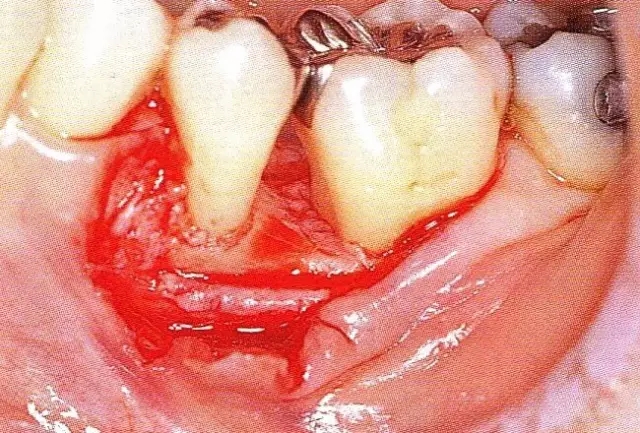

640.webp (3).jpg

▲圖7-4  術(shù)后1年2個(gè)月再翻開看的情況。與圖7-1的骨缺損狀態(tài)相比可知形成了臨床性骨再生。

640.webp (4).jpg

▲圖7-5  此狀態(tài)下,左下5的遠(yuǎn)中存在牙槽骨不平整,因此進(jìn)行了骨修整。同時(shí),將骨膜留存,進(jìn)行了齦瓣根尖側(cè)移動(dòng)術(shù),去除了牙周袋。